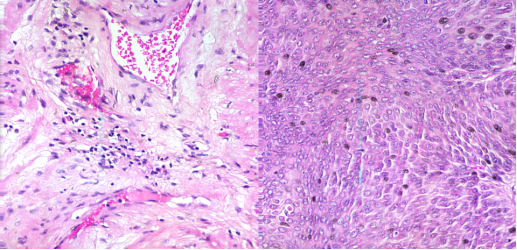

(a)100X宮頸癌非腫瘤切片;(b)100X宮頸癌腫瘤切片

(a)40×膀胱癌非腫瘤切片;(b)40×膀胱癌腫瘤切片

醫用顯微成像光譜儀數據